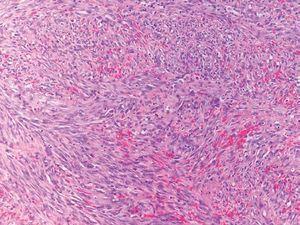

Fig. 3.--Biopsia de lesión de sarcoma de Kaposi. A mayor aumento se observan abundantes células fusiformes agrupadas en fascículos entrelazados con eritrocitos salpicados en el intersticio.